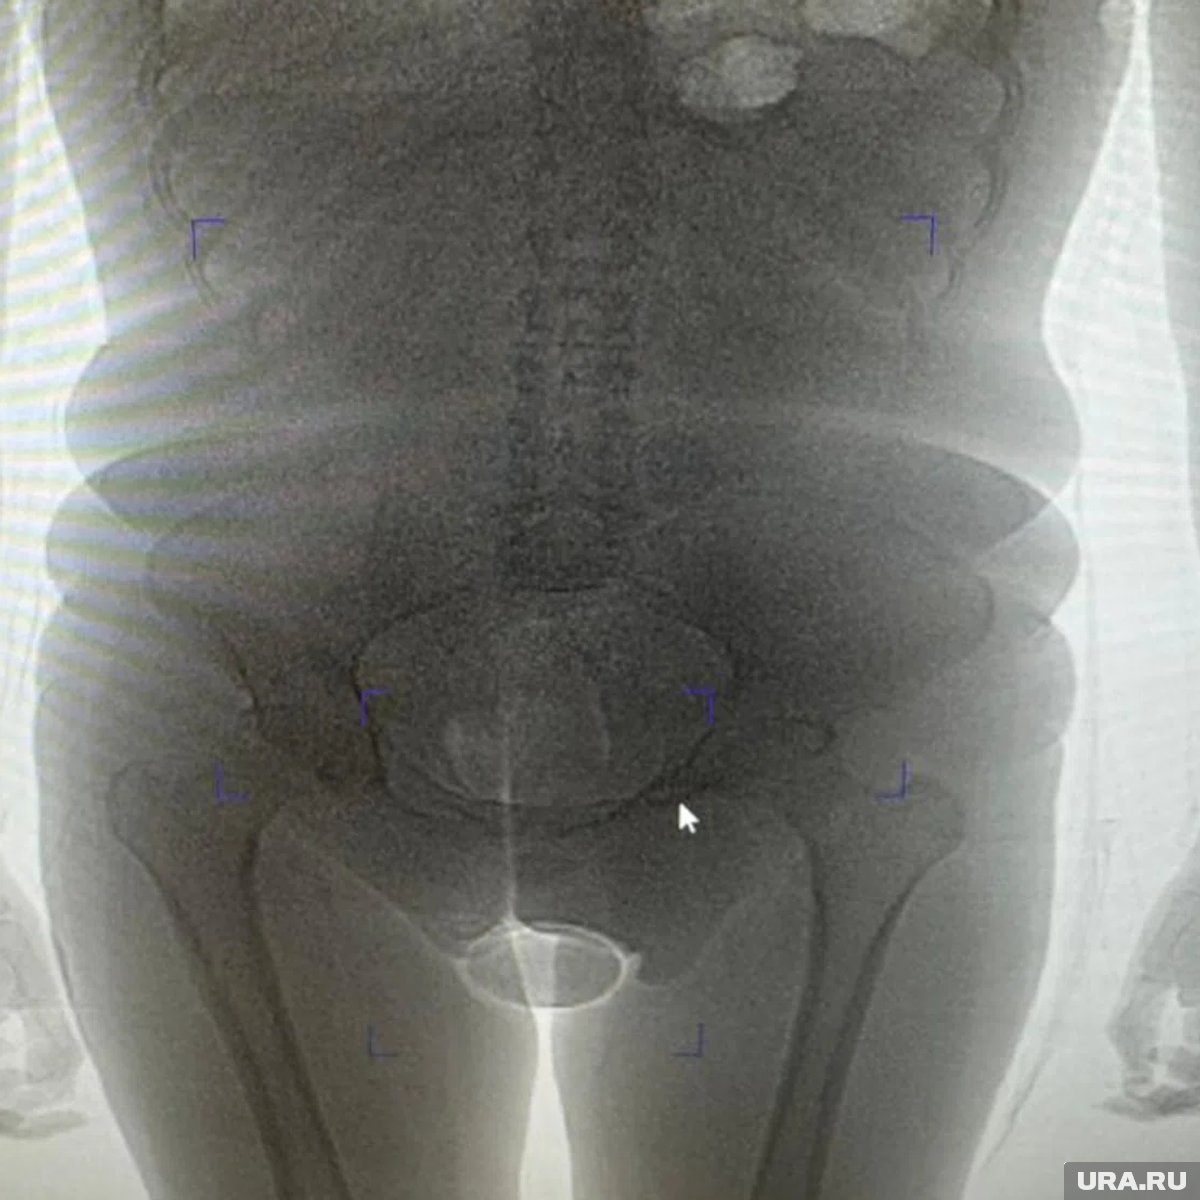

«В результате проведения таможенного досмотра обнаружено два презерватива с порошкообразным веществом внутри, один из которых находился в нижнем белье пассажирки, второй сокрыт внутриполостным способом», — говорится в заявлении пресс-секретаря. Информация есть в распоряжении URA.RU.

Девушка пояснила, что вещество представляет собой кокаин, который она согласилась перевезти по просьбе неустановленного мужчины за денежное вознаграждение. Проведенная экспертиза подтвердила, что изъятое вещество является кокаином общей массой 250 граммов. Сейчас иностранка заключена под стражу. В отношении нее возбуждено уголовное дело по статье о контрабанде наркотических средств в особо крупном размере. Санкция данной статьи предусматривает лишение свободы на срок от 15 лет до пожизненного заключения с возможным штрафом до одного миллиона рублей.